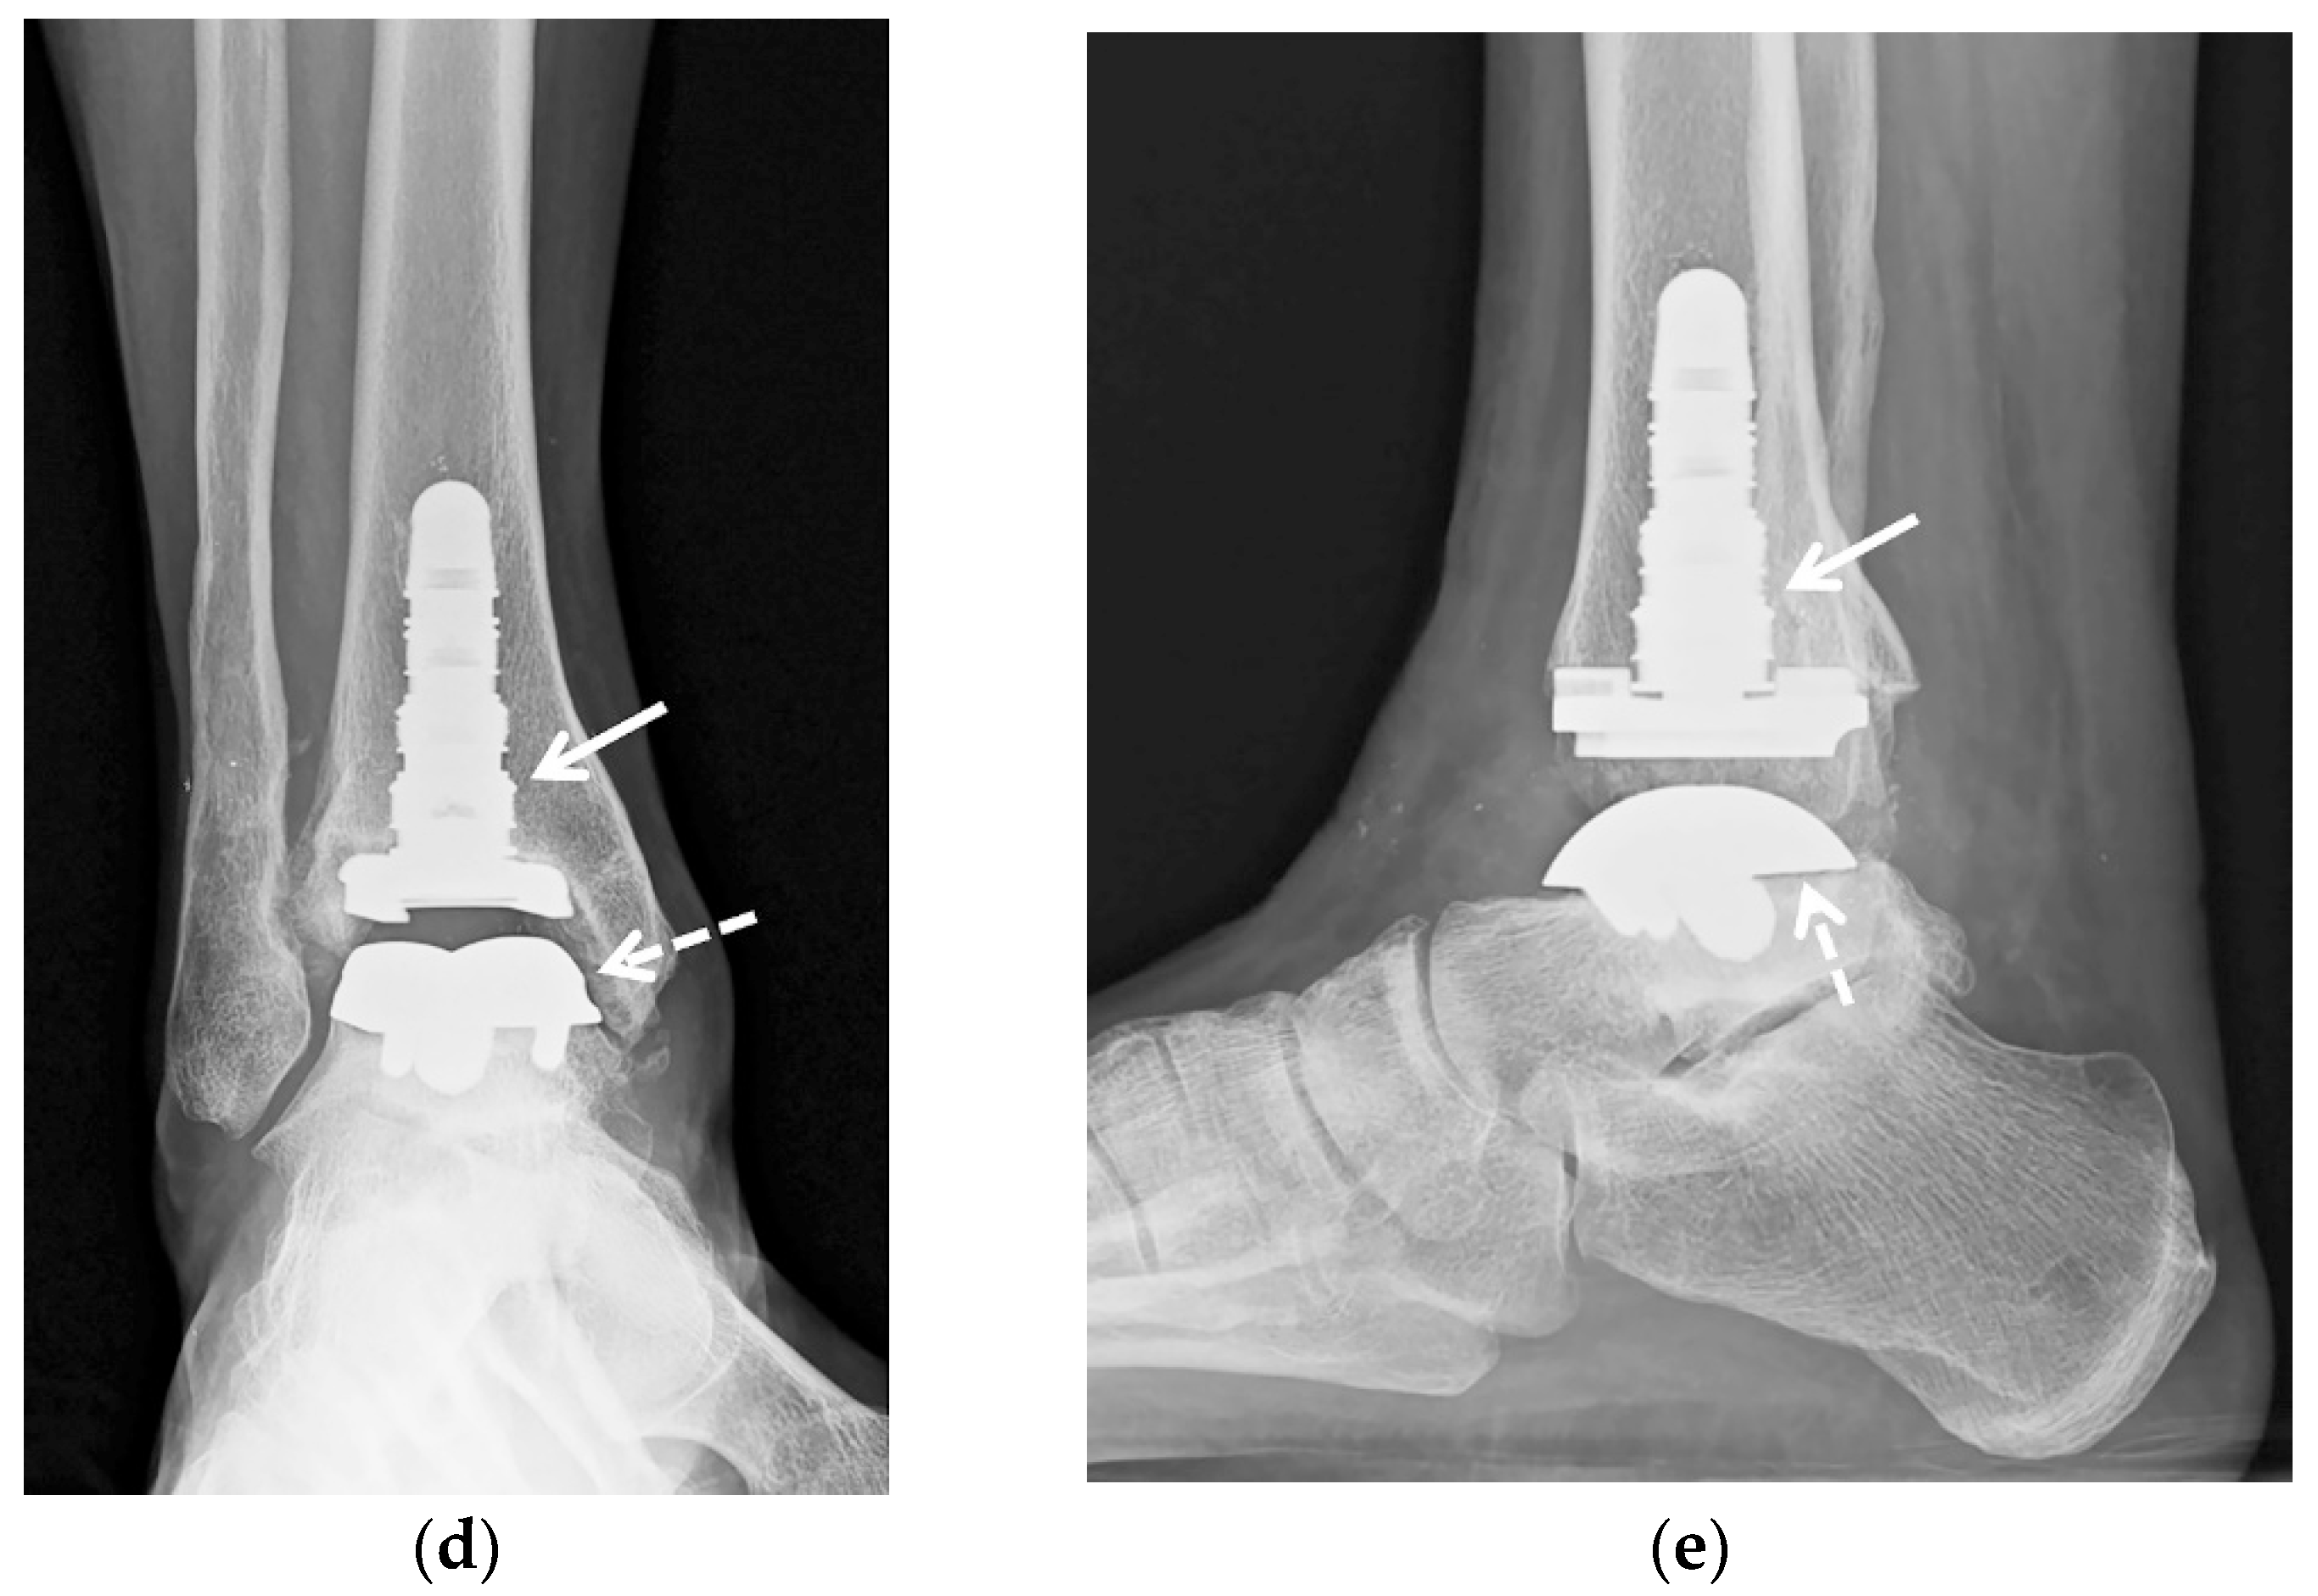

5.2.3. Ankle Arthroplasty